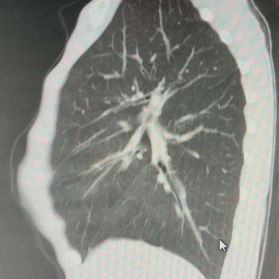

Preoperative Examination

The patient's chest wall protrudes significantly, with the central part being the most pronounced and forming an acute angle deformity. Additionally, there are depressions on both sides of the lower half of the chest wall. The patient was diagnosed with severe complex chest wall deformities.